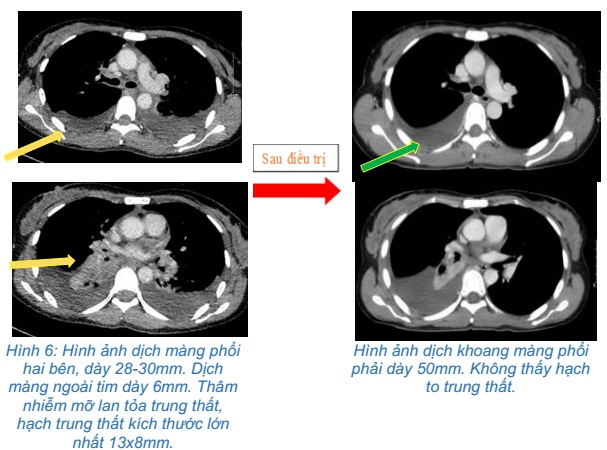

- Chụp cắt lớp vi tính ngực: Rốn phổi phải có đám thâm nhiễm kích thước 28x32mm, ranh giới không rõ, gây hẹp lòng và cắt cụt một số nhánh phế quản thùy dưới. Thùy trên phổi phải có nhiều nốt đặc, đám mờ kích thước lớn nhất 14x8mm. Dịch màng phổi hai bên, dày 28-30mm. Dịch màng ngoài tim dày 6mm. Thâm nhiễm mỡ lan tỏa trung thất, hạch trung thất kích thước lớn nhất 13x8mm.

Hình ảnh dịch màng phổi hai bên, dày 28-30mm. Dịch màng ngoài tim dày 6mm. Thâm nhiễm mỡ lan tỏa trung thất, hạch trung thất kích thước lớn nhất 13x8mm

- Chụp cắt lớp vi tính ngực:Khối vùng rốn phổi phải gây xẹp phổi kích thước 28x32mm. Dịch khoang màng phổi phải dày 50mm. Khống thấy hạch to trung thất

So sánh hình ảnh cắt lớp vi tính ngực trước và sau điều trị 3 chu kỳ: